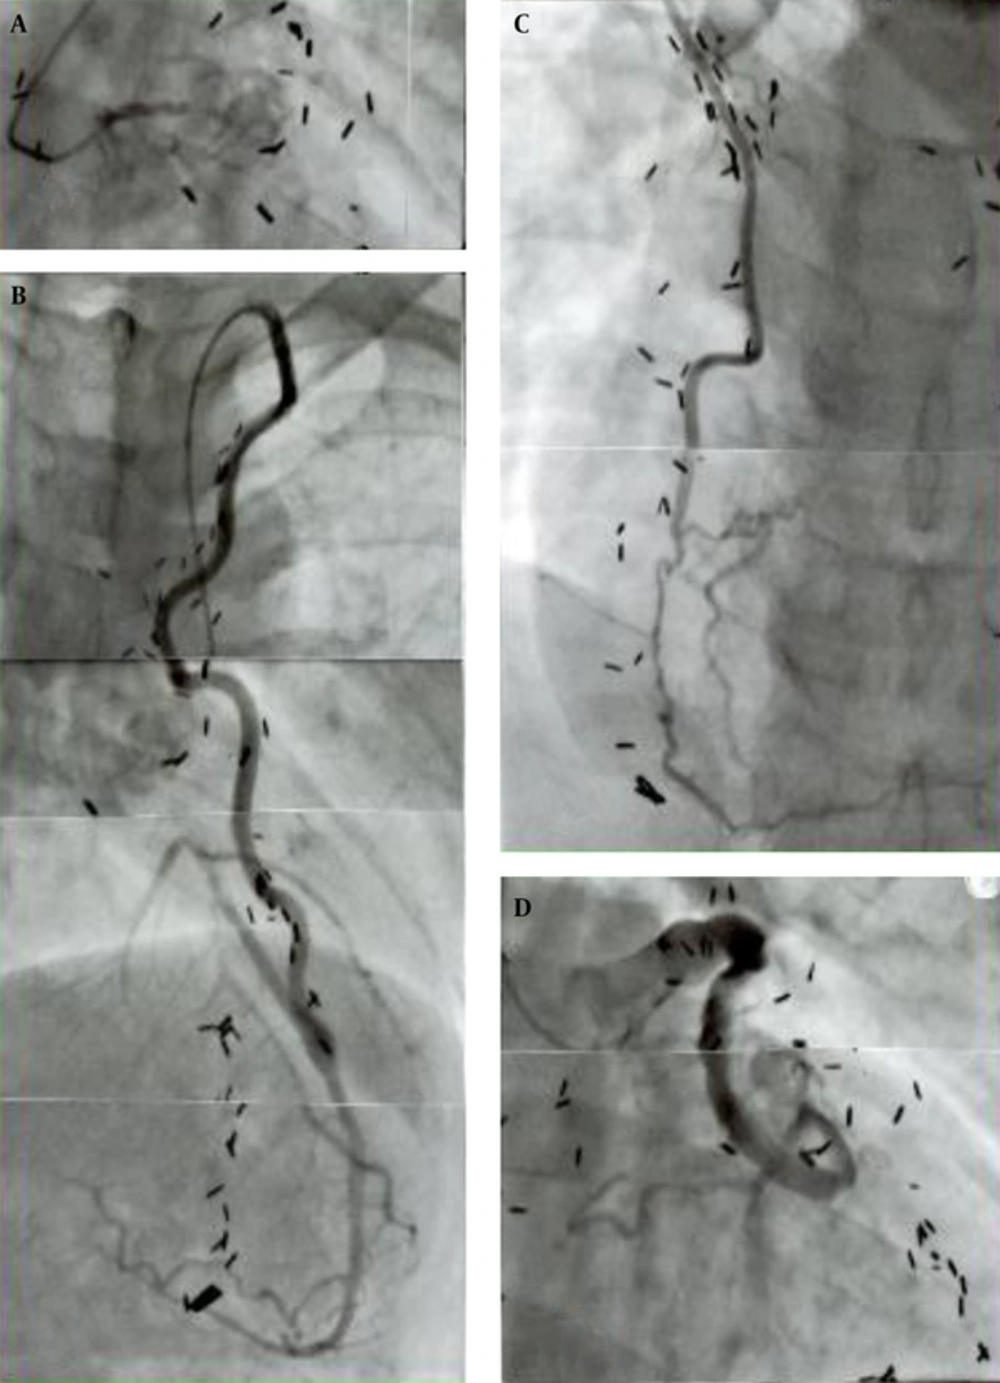

Late postoperative angiographic graft morphology was quite different between the SVG and ITA. The wall configuration of the ITA graft was smooth with no luminal stenosis or dilatation and well matched in size with that of the recipient coronary artery area 20 years after the operation (21, 24). In addition, the graft length grew in proportion to the patient body growth (24, 30, 31). In contrast, the SVG was usually dilated with a local narrowing and was sometimes aneurysmal with prominent irregularity of the wall contour (22, 24). Patients in their twenties showed fibro proliferative thickening and atherosclerotic changes with mural thrombosis (22, 24, 33). The SVG could also be a cause of acute myocardial infarction in the late postoperative period probably due to embolism from wall thrombus detachment or thrombosis at the site of intimal thickening. Because of the poor growth potential of SVGs, they could cause traction on the recipient coronary artery distorting the anastomosis, resulting in poor run-off to the distal artery (20, 21). The representative graft-coronary angiograms in the late postoperative period (> 20 years) are shown in Figure 3.

The boy received a triple bypass grafting at age 12 years for coronary lesions due to KD, his bilateral coronary ostia or very proximal main trunks had been totally obstructed (A); he sustained an acute myocardial infarct due to SVG-LCX artery thrombosis that occurred 24 years after the operation (D); fortunately, bilateral ITAs (LITA-LAD, RITA-RCA) were well patent (B, C) and the patient survived without complication; thrombolysis of the SVG was successfully carried out. Note the difference in configuration and wall characteristics of the ITA (B, C) and SVG (D) 24 years after the operation; presence of old SVG itself can be a cause of acute myocardial infarction; A, total obstruction of the left main trunk; B, left internal thoracic artery (LITA) -left anterior descending artery (LAD); C, right internal thoracic artery (RITA) -right coronary artery (RCA); D, saphenous vein graft (SVG) -left circumflex artery (LCX).